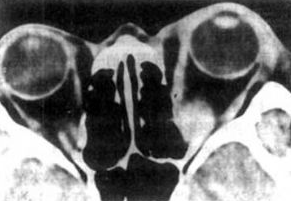

您的位置首页百科知识 浸润性突眼 Simone 发布于 2025-10-01 13:38:52 941 阅读 浸润性突眼的有关信息介绍如下:浸润性突眼:又称内分泌性突眼、眼肌麻痹性突眼症或恶性突眼,较少见病情较严重,可见于甲亢不明显或无高代谢症的患者中,主要由于眼外肌和球后组织体积增加、淋巴细胞浸润和水肿所致。想要了解更多“浸润性突眼”的信息,请点击:浸润性突眼百科